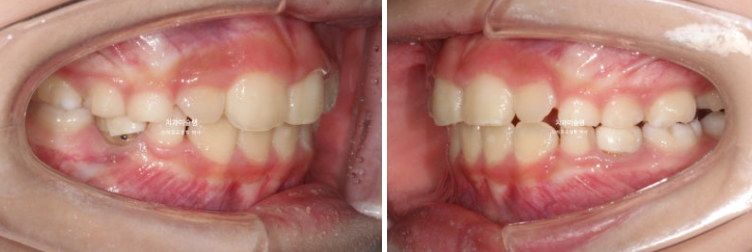

23년 10월, 교정치료를 위해 온 어린이 입니다.

앞니 두 개 높낮이 차이, 앞니가 깊게 물리는 과개교합이 보입니다.

앞니 네개 중 옆 앞니 즉 측절치가 나올 공간이 좁습니다.

아래도 마찬가지 입니다.

앞니가 벌써 삐뚤삐뚤 합니다.

송곳니가 나올때는 어떻게 될까요?

덧니 100% 예약입니다.